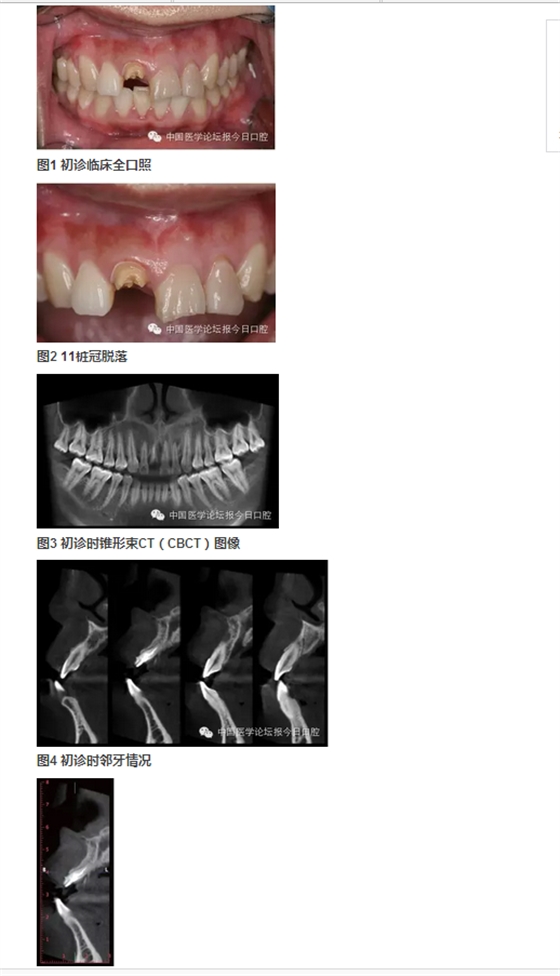

北京大學(xué)口腔醫(yī)院種植科 在唇側(cè)和舌側(cè)牙槽突骨板骨折的病例中,唇/舌側(cè)牙槽突發(fā)生相應(yīng)的骨吸收。長期的臨床經(jīng)驗告訴我們,唇側(cè)和舌側(cè)骨板的低位骨折,任其常規(guī)牙槽窩愈合,會導(dǎo)致三維方向的骨缺損。根據(jù)ITI機構(gòu)的SCA分類,伴有垂直和水平骨缺損的病例,則是復(fù)雜和高難度病例,美學(xué)風(fēng)險極大。即刻種植無法預(yù)防和避免骨吸收。 在本病例中,我們采用符合富血小板纖維蛋白(PRF)技術(shù)的牙槽窩位點保存技術(shù),最大限度保存局部骨量。以及采用輪廓擴增的引導(dǎo)骨再生(GBR)技術(shù)同期種植重建了種植位點的三維骨結(jié)構(gòu),通過暫時冠誘導(dǎo)穿齦輪廓和牙齦乳頭形態(tài),最終獲得患者滿意的美學(xué)修復(fù)。 女性,27歲。以“右上前牙樁冠修復(fù)11年,脫落1周”為主訴前來就診。 11年前,患者前牙外傷,于當(dāng)?shù)蒯t(yī)院行11、21、22根管治療及11樁冠修復(fù)。1周前11樁冠脫落,于多家醫(yī)院修復(fù)科就診,以“11牙槽突骨折”的診斷,無法保留11殘根,建議拔除,而前來就診。 既往體健,否認(rèn)系統(tǒng)性疾病史及藥物過敏史。 臨床檢查可見11殘根,21、22牙冠變色。前牙區(qū)咬合略緊,Ⅱ度深覆牙合。CBCT示上頜右側(cè)中切牙頰側(cè)根頸1/3骨板折裂。21、22牙冠變色。前牙區(qū)咬合略緊,Ⅱ度深覆牙合。CBCT示上頜右側(cè)中切牙頰側(cè)根頸1/3骨板折裂。21、22根尖病變,前牙區(qū)牙槽突根方骨量不足。 圖6 舌側(cè)骨缺損的3D重建 診斷 ①右上中切牙牙槽突骨折(?);② 左上中切牙、側(cè)切牙慢性根尖炎;③Ⅱ度深覆牙合。 病例特點與難點 ①樁冠修復(fù)失敗后的三維骨缺損(頰/舌側(cè)骨板折裂、牙槽骨根方骨量不足);②年輕女性,美學(xué)要求較高;③ 鄰牙根尖周病變;④輕度深覆牙合,咬合略緊。上頜骨基底骨骨量不足,正畸醫(yī)師不建議矯正。 治療設(shè)計 ①正畸會診,希望下前牙下壓,改善咬合緊,深覆牙合;② 左上中切牙、側(cè)切牙根管治療,必要時行根尖手術(shù),貼面修復(fù)改善美觀;③ 右上中切牙牙槽窩位點保存,根據(jù)牙槽嵴骨量保持情況,確定二期種植和植骨以及必要的軟組織整理和塑形。 1.正畸科醫(yī)師會診,因患者上頜牙槽骨基底骨骨量不足,多數(shù)牙齒唇側(cè)骨板不足或缺失,正畸風(fēng)險大而建議放棄正畸治療。 2.因無法進(jìn)行正畸治療,故需要合理的種植位點和修復(fù)方式,以適應(yīng)患者的咬合情況。 3.牙體牙髓科醫(yī)師會診,進(jìn)行左上中切牙、側(cè)切牙根管治療后隨訪,根據(jù)愈合情況決定是否進(jìn)行根尖手術(shù)。 4.右上中切牙牙槽窩位點保存+富血小板纖維蛋白(PRF)技術(shù)。 5.6個月后行種植+引導(dǎo)骨再生(GBR)。 6.愈合4個月后,行軟組織增量和塑形,擇期永久修復(fù)。 7.愈合期內(nèi),以馬里蘭橋或壓膜過渡義齒臨時修復(fù)。 8.左上中切牙、側(cè)切牙貼面修復(fù)改善美觀。 ④ Bio-Oss®; ⑤ NobelProcera全瓷修復(fù)。 ①左上中切牙、側(cè)切牙經(jīng)根管治療后,根尖病變隨訪期內(nèi)縮小并逐漸消失,避免了進(jìn)一步的根尖手術(shù); ②右上中切牙牙槽窩位點保存+PRF技術(shù)治療,避免了牙槽嵴可能發(fā)生的三維方向骨缺損,極大限度保持和原位重建局部骨量; ③在種植位點軟組織和硬組織無缺損的情況下,在較佳的三維位點植入種植體,同期GBR行輪廓擴增的骨增量技術(shù),應(yīng)用低替代率的骨代用品,獲得較好的長期穩(wěn)定性; ④左上中切牙、側(cè)切牙貼面修復(fù)美學(xué)效果較好; ⑤經(jīng)過治療和口腔健康宣教,患者口腔衛(wèi)生情況得到較大提高; ⑥在妊娠期齦炎時,修復(fù)體和天然牙周圍的牙齦不同程度受累,但是種植修復(fù)體周圍牙齦穩(wěn)定,點彩未消失。 ①適宜技術(shù)的選擇,序列治療計劃的選擇、制定和執(zhí)行,在口腔種植美學(xué)修復(fù)中具有很重要的意義。 ②錐形束CT在口腔種植的臨床診斷和治療設(shè)計中起到了重要的作用。 ③符合PRF技術(shù)的牙槽窩位點保存技術(shù),充分應(yīng)用了PRF技術(shù)在軟組織愈合上的優(yōu)勢。經(jīng)PRF膜技術(shù)在封閉牙槽窩的同時,促進(jìn)牙齦上皮的生長。在局部軟組織愈合的條件下,進(jìn)一步促進(jìn)骨組織的生長。從而最大限度地保存了種植位點的骨量。 ④輪廓擴增的GBR技術(shù)使用過增量的植骨,自體骨+低替代率骨代用品+可吸收膠原膜+可靠的膜釘固定技術(shù),從而重建出種植體周圍健康的軟硬組織形態(tài)。 ⑤暫時冠技術(shù),對于穿齦輪廓的誘導(dǎo)和成型具有良好效果。 ⑥經(jīng)過序列治療的種植修復(fù),具有較好的美學(xué)效果和長期穩(wěn)定性,在妊娠期齦炎,隨著激素水平的變化,上頜前部美學(xué)區(qū)天然牙和修復(fù)體周圍出現(xiàn)不同程度的水腫,但是種植體周圍牙周健康,點彩存在。 周磊教授: 位點保存技術(shù)包含軟組織與硬組織的保存。通常牙缺失后牙槽嵴在1個月之內(nèi)軟組織修復(fù)重建,而硬組織尚未明顯吸收。但這個時期如不給予人為干預(yù),軟組織修復(fù)常陷于牙槽窩內(nèi),形成凹陷,不利于植入種植體后的軟組織成形及傷口的關(guān)閉。 國際口腔種植學(xué)會前任主席Buser介紹的完整的位點保存技術(shù)是:拔牙后植入膠原骨,1個月以后軟組織重建修復(fù)形成較為豐滿的外形,然后再切開,將牙槽窩內(nèi)殘存的膠原骨刮除,植入骨粉3~6個月后再行種植體植入,這樣確保了拔牙位點豐滿的外形。 軟硬組織修復(fù)重建分兩步進(jìn)行的原因是:膠原骨有較好的細(xì)胞趨化特性,可促進(jìn)鄰近的牙齦組織生長進(jìn)入,但膠原骨會較快吸收,在其完成誘導(dǎo)軟組織生長任務(wù)后,更換為吸收速率較低的充填材料(Bio-Oss小牛無機骨粉)更利于硬組織的修復(fù)重建及重建后穩(wěn)定性;如直接選用吸收速率較低的充填材料一次完成位點保存,由于軟組織量不足,在牙槽嵴頂部常難維持骨粉的位置。 該病例屬于軟組織的位點保存,可看到,二期手術(shù)時,軟組織已較豐富,但翻開后可見硬組織,既無明顯的重建也無明顯的吸收,在植入種植體后,可將傷口理想地關(guān)閉。